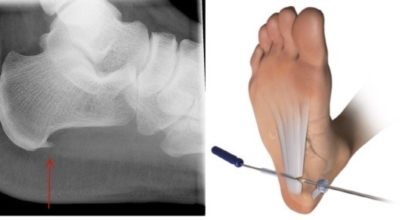

비수술적 치료로 대부분 족저 근막염 증상이 완화될 수도 있지만 일부 환자는 수술이 필요한 경우가 있어요. 수개월간의 비수술적 치료를 했음에도 발 통증이 계속되면 수술을 고려해봐야 하며 수술을 통해 족저 근막을 증가시키는 방법을 고려해 볼 수 있다고 해요.

최근 관절경을 이용해 족저 근막 절개술을 시도하기도 하는데 수술적 치료의 성공률은 70~90%로 높게 알려져 있어요. 하지만 수술 후 신경 훼손 등과 같은 합병증이 유발될 수 있기 때문에 잘 알아보고 전문의와 상담후 수술을 결정하시는게 좋답니다.